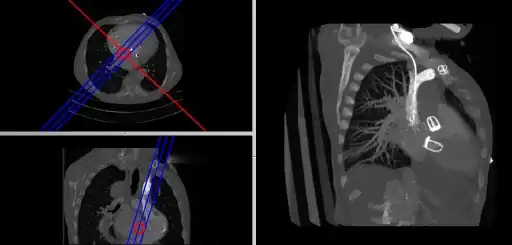

- Composite MPR Display

- Coronal and sagittal reconstructions are referred to as Orthogonal MPRs because the perspectives generated are from planes of image data which are at right angles to each other. Composite MPR displays can be generated so that linked cursors or crosshairs can be used to locate a point of interest from all three perspectives, as illustrated in these images:

![]() |

- This form of image presentation is sometimes referred to as a TCS display – implying the viewing of Transaxial, Coronal and Sagittal slices. It can be combined with the slice projection methods we discussed earlier, as illustrated in the two sets of images below, where the blue lines highlight the limits of the coronal projections:

- Here the plane can be defined in, say, the axial images (red line, top left) and a maximum intensity projection (the limits used are highlighted by the blue lines), for example, can be displayed for the reconstructed plane (right). This technique is useful when attempting to generate perspectives in cases where the visualization of three-dimensional structures is complicated by overlapping anatomical detail.